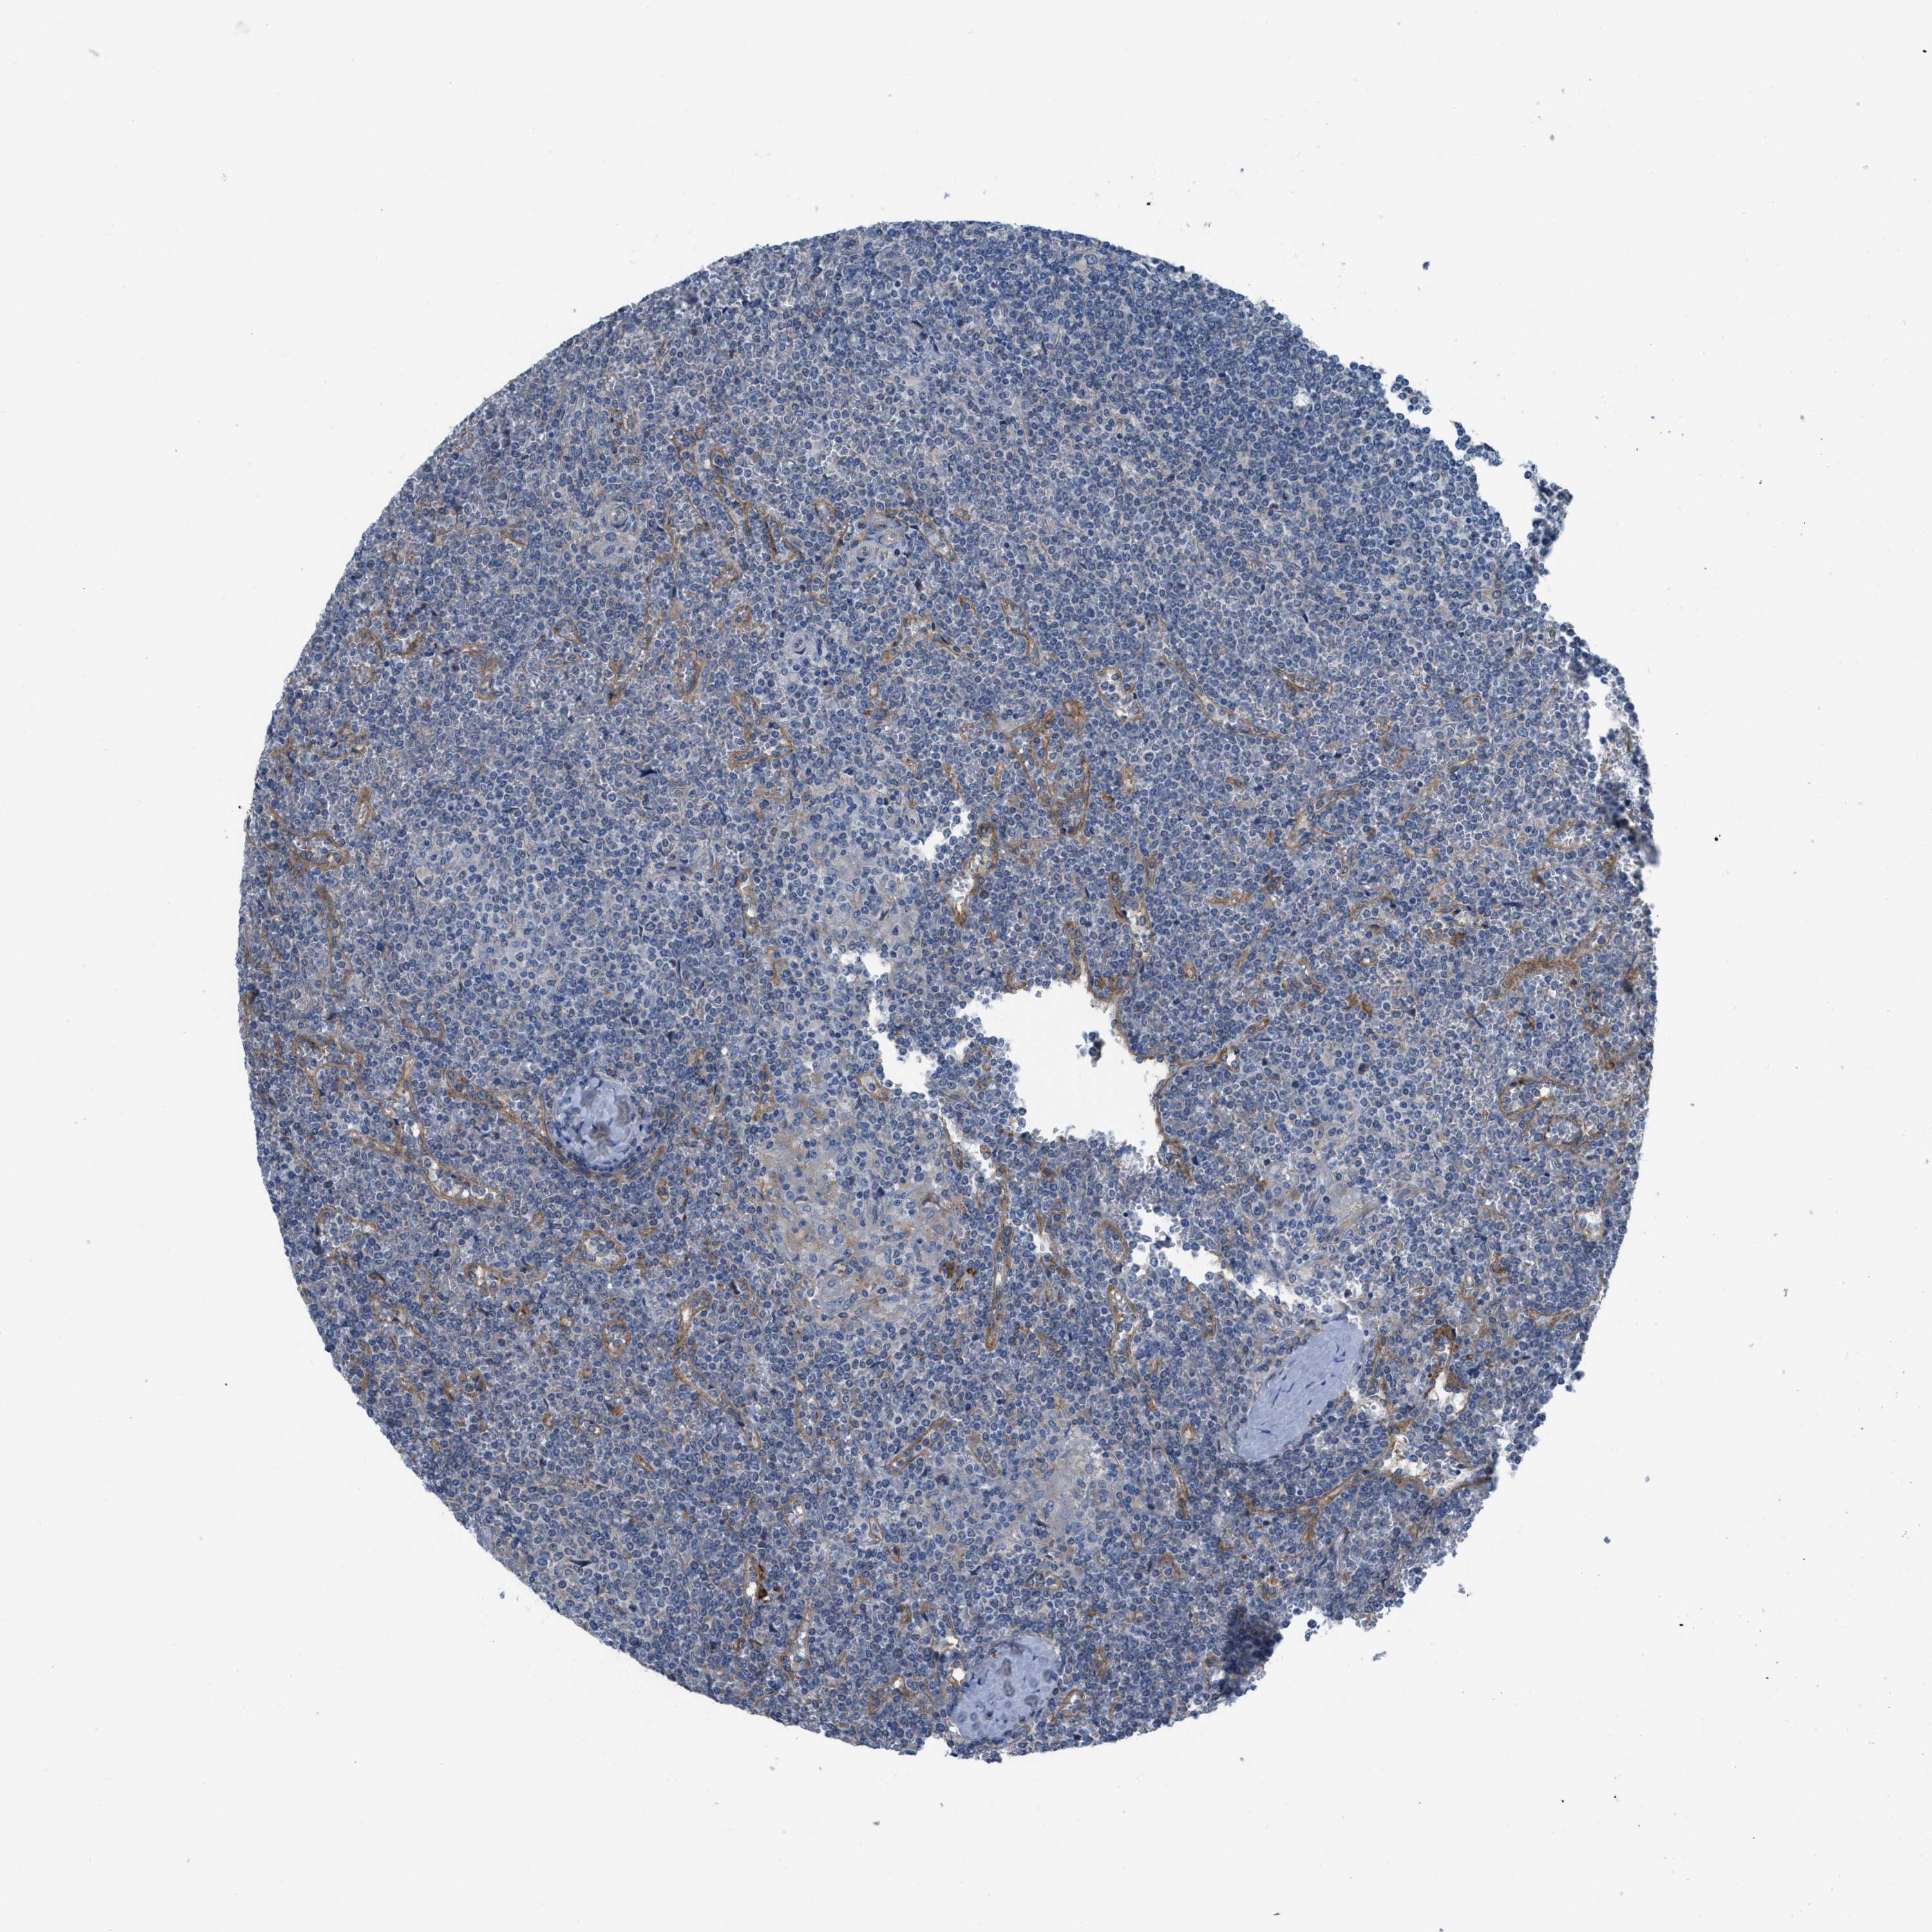

CANCER LYMPHOMA Show tissue menu

LYMPHOMA - Protein expressioni

A mouse-over function shows sample information and annotation data. Click on an image to view it in a full screen mode. Samples can be filtered based on level of antibody staining by selecting one or several of the following categories: high, medium, low and not detected. The assay and annotation is described here.

Antibody stainingi

Antibody staining in the annotated cell types in the current human tissue is reported as not detected, low, medium, or high, based on conventional immunohistochemistry profiling in selected tissues. This score is based on the combination of the staining intensity and fraction of stained cells.

Each image is clickable and will lead to virtual microscopy that enables deeper exploration of all samples and also displays staining intensity scores, fraction scores and subcellular localization as well as patient and tissue information for each sample.

Malignant lymphoma, non-Hodgkin's type, High grade

Hodgkin's disease, NOS

Malignant lymphoma, non-Hodgkin's type, Low grade